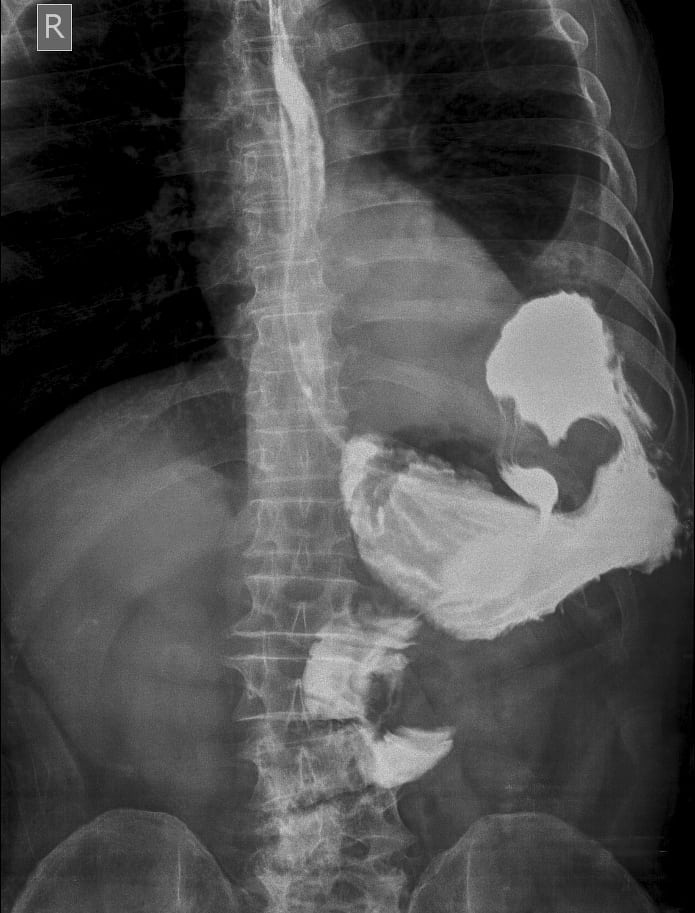

Xoắn dạ dày

Xoắn dạ dày - Ảnh 3

» Thông tin: Nam giới – 60 tuổi.

» Lâm sàng: Đau bụng cấp + Nôn.